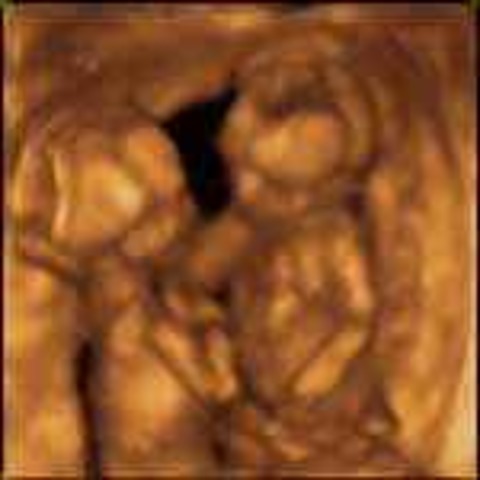

• Week 27 (Start of the third trimester)

The baby's muscle tone is improving and fat is continuing to grow. The brain continues its rapid growth.

FUN FACT: The fetus weighs almost 2 pounds.